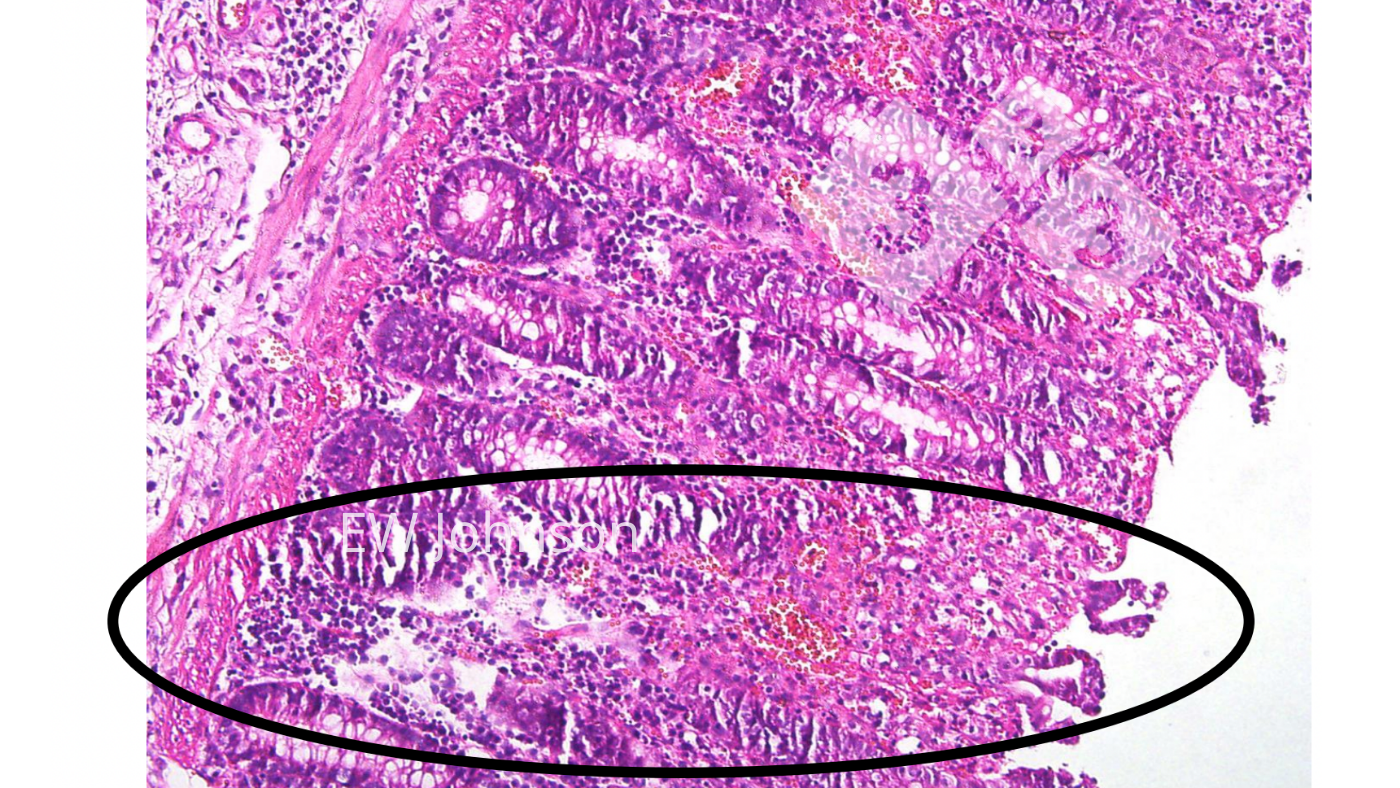

No exame histopatológico é observada uma vasculite generalizada com infarto, hemorragia e trombose em diversos orgãos, particularmente no pulmão, baço, nódulos linfáticos, rins, cérebro e intestino. Há uma destruição linfóide massiva nos nódulos linfáticos e baço e vacuolização dos macrófagos alveolares. É frequente a necrose e a ulceração do epitélio do cólon (foto 4).

O uso da histopatologia para verificar as lesões crónicas típicas da vacina com genes deleteados pode ser muito útil. Os porcos que receberam essas vacinas de PSA frequentemente apresentam lesões vasculares fibrosantes e cicatriciais crónicas activas, incluindo trombos e infartos no intestino, fígado, tecidos linfóides, coração e rins. Os nódulos linfáticos podem apresentar áreas hemorrágicas, com necrose e destruição de linfócitos e áreas com fibrose e cicatrização. Os reprodutores vacinados podem apresentar grandes áreas de necrose e fibrose pulmonar que muitas vezes são confundidas com App crónica. O vírus da vacina pode não matar o porco, mas o porco muitas vezes é incapaz de libertar o vírus da vacina.